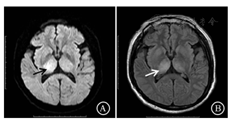

35例成人乙脑患者的MRI显示,初期11例(31.4%),极期19例(54.3%),恢复期5例(14.3%)。初期乙脑患者中,DWI高信号9例,病灶边界均清晰(图1A),FLAIR稍高信号2例,1例病灶边界清晰(图1B);极期乙脑患者中,DWI高信号16例(13例病灶边界清晰),FLAIR稍高信号11例(9例病灶边界清晰),T1WI高信号3例及T2WI高信号6例;恢复期患者中,DWI稍高信号1例,病灶边界模糊,FLAIR高信号5例,病灶边界均清晰,T2WI高信号1例。

注:A.DWI双侧丘脑高信号(黑色箭头),病灶边界清晰;B.FLAIR双侧丘脑稍高信号(白色箭头),病灶边界模糊